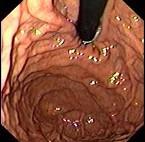

问题 女,28岁,反复上腹痛4年,早饱嗳气,无黑便史,便秘腹泻交替,胃镜检查如图,近来B超肝胆脾胰未见异常。最可能的诊断 ( )

选项 A.功能性消化不良, B.慢性胰腺炎, C.消化性溃疡 D.十二指肠球炎 E.弥漫性胃癌

答案 A